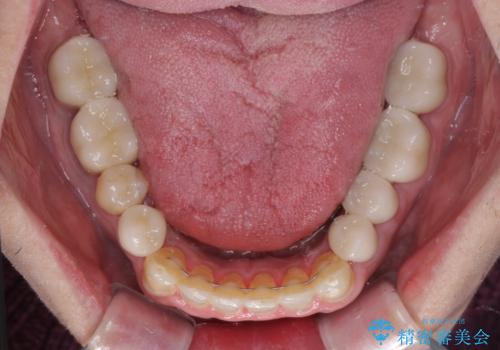

- 飛び出している上顎前歯と、奥歯に多くある銀歯を気にして来院された患者様です。

マウスピースで矯正を行いたい反面、一旦早めに前歯を整えたいというご希望があったため、まずは上顎前歯をワイヤー装置で整え、その後インビザラインにて仕上げていくこととしました。

矯正治療後には、奥歯の銀歯をすべてセラミックにて補綴治療することとしました。

ワイヤー矯正を併用したことで、上顎前歯はあっという間に整いました。

補綴治療にあたり、痛みのある歯に対して根管治療を行うこととしましたが、処置が必要な歯が多かったため、期間を要しました。

補綴治療中に前歯のデコボコが戻ってしまったため、補綴治療後にインビザラインを1セット追加して仕上げました。